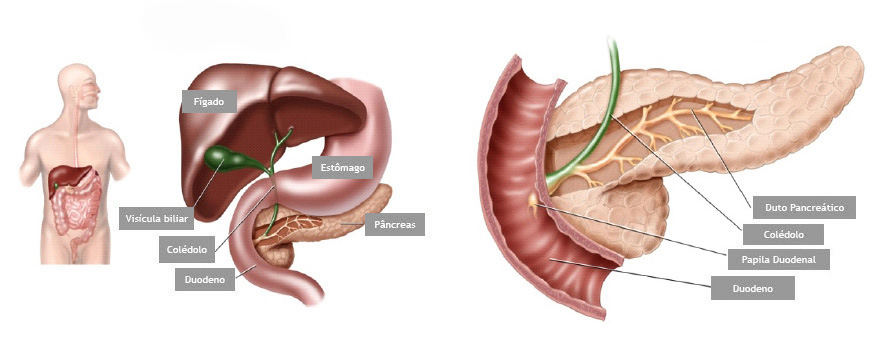

A CPRE é um procedimento que pode ser feito para examinar o fígado, vesícula biliar, vias biliares e o pâncreas. O fígado é um órgão que, entre outras coisas, produz um líquido chamado bile que auxilia a digestão. A vesícula biliar é um órgão pequeno, em forma de pêra, que armazena a bile até que seja necessária para a digestão. Os ductos biliares são canais que transportam a bile do fígado para a vesícula biliar e duodeno. Estes ductos são chamados algumas vezes de árvore ou via biliar. O pâncreas é um órgão que produz substâncias químicas que ajudam a digestão.

Com o paciente sedado, o aparelho é introduzido pela boca e passa através do esôfago e do estômago para o duodeno, local onde fica posicionada a papila duodenal.

Para o exame, o médico utiliza um tubo flexível e iluminado chamado duodenoscópio, que possui uma câmera na lateral do aparelho, diferente do endoscópico padrão que possui a câmera na frente do aparelho.

O médico verifica a abertura do tubo de drenagem de bile do fígado. Este tubo de drenagem é chamado de ducto biliar comum. Drena bile do fígado e suco pancreático para o duodeno para ajudar na digestão das gorduras. O orifício de saída do ducto biliar no parede do duodeno chama-se papila duodenal.

Durante o exame o médico passa de um pequeno cateter (tubo) dentro do ducto biliar comum e injeta um contraste que pode ser visto com um exame de raio-X. A via biliar e eventualmente o pâncreas podem então ser examinados para anormalidades.

A CPRE pode ser utilizada para o tratamento de pedras ou bloqueios nos canais biliares. Seu médico pode usar alguns acessórios para fazer um pequeno corte na parede do intestino, na abertura do duto biliar comum para alargar a abertura da papila duodenal. Este procedimento chama-se papilotomia endoscópica.

A CPRE é um procedimento que pode ser feito para examinar o fígado, vesícula biliar, vias biliares e o pâncreas. O fígado é um órgão que, entre outras coisas, produz um líquido chamado bile que auxilia a digestão. A vesícula biliar é um órgão pequeno, em forma de pêra, que armazena a bile até que seja necessária para a digestão. Os ductos biliares são canais que transportam a bile do fígado para a vesícula biliar e duodeno. Estes ductos são chamados algumas vezes de árvore ou via biliar. O pâncreas é um órgão que produz substâncias químicas que ajudam a digestão.

Com o paciente sedado, o aparelho é introduzido pela boca e passa através do esôfago e do estômago para o duodeno, local onde fica posicionada a papila duodenal.

Para o exame, o médico utiliza um tubo flexível e iluminado chamado duodenoscópio, que possui uma câmera na lateral do aparelho, diferente do endoscópico padrão que possui a câmera na frente do aparelho.

O médico verifica a abertura do tubo de drenagem de bile do fígado. Este tubo de drenagem é chamado de ducto biliar comum. Drena bile do fígado e suco pancreático para o duodeno para ajudar na digestão das gorduras. O orifício de saída do ducto biliar no parede do duodeno chama-se papila duodenal.

Durante o exame o médico passa de um pequeno cateter (tubo) dentro do ducto biliar comum e injeta um contraste que pode ser visto com um exame de raio-X. A via biliar e eventualmente o pâncreas podem então ser examinados para anormalidades.

A CPRE pode ser utilizada para o tratamento de pedras ou bloqueios nos canais biliares. Seu médico pode usar alguns acessórios para fazer um pequeno corte na parede do intestino, na abertura do duto biliar comum para alargar a abertura da papila duodenal. Este procedimento chama-se papilotomia endoscópica.